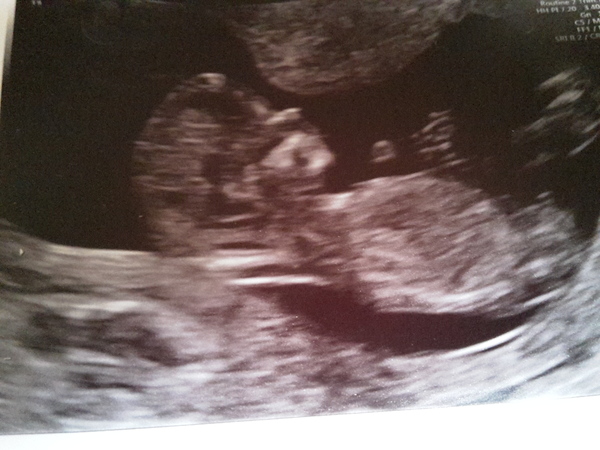

So I met this little one this morning measuring bang on 12+4 as per my own dates. All feeling a bit more real now.

Ahhhhh co5mo brilliant! Lovely scan Smile

Oh Co5mo congrats, what a lovely photo.

Thanks. Took nearly half an hour of prodding poking and jumping around to get it to move it's hands away from it's face.

Cosmo, that's a lovely scan picture! And you obviously had your calculations just right!!

Congratulations Co5mo! Gorgeous scan pic!

Woohoo Cosmo that's a lovely picture Grin